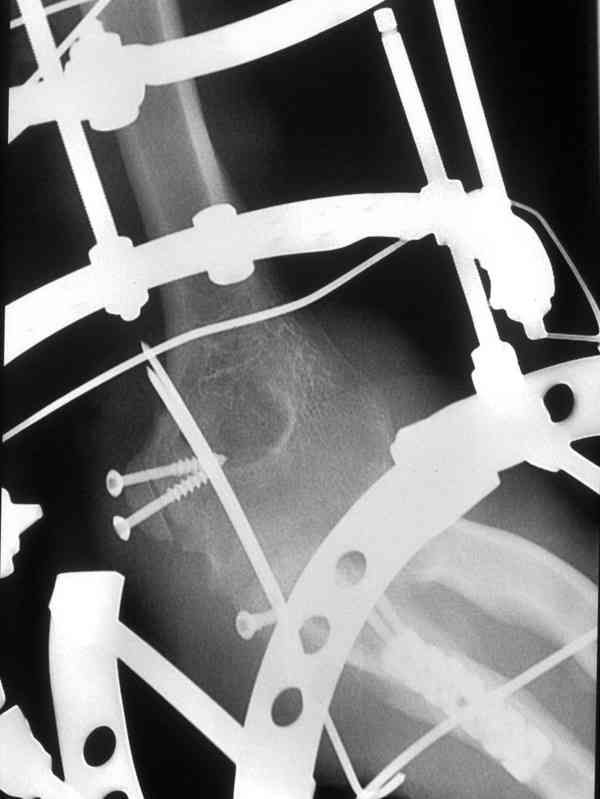

[Ortho] Несросшийся перелом локтевой кости, подвывих предплечья кзади.Перелом венечного отростка. Состояние после резекции головки лучевой. Травма 4 мес. назад.

Больной был прооперирован.Протеза головки лучевой у нас нет. Решили с

локтевой костью пока ничего не делать. Выполнили операцию

по востановлению связочного аппарата локтевого

сустава(см.схему)-модфикация метода W.E.Spring,сухожилие мы

фикстровали к винту на локтевой. Естественно ревизия сустава и

удаление рубцово-хрящевидных тканей.Затем наложили аппарат Илизарова с

шарнирами. Первые 2 дня сустав был фиксирован трансартикулярно 2-мя

спицами, затем спицы удалили. И больной начинает движения в аппарате.

Прилагаюся послеоперационные рентгенограммы.

Планиуем аппарат на 3-4 нед.